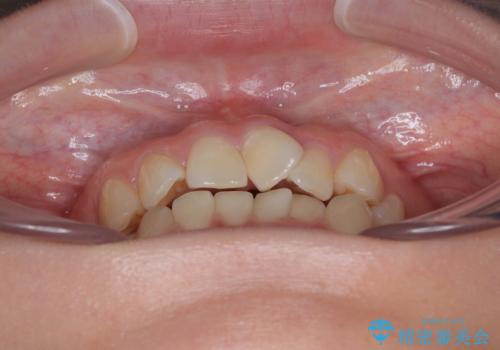

診察の結果、上下の前歯部に**叢生(そうせい/歯のガタガタ・重なり)**が認められました。

特に上の前歯にはねじれや重なりがあり、審美的にも清掃性にも影響している状態でした。